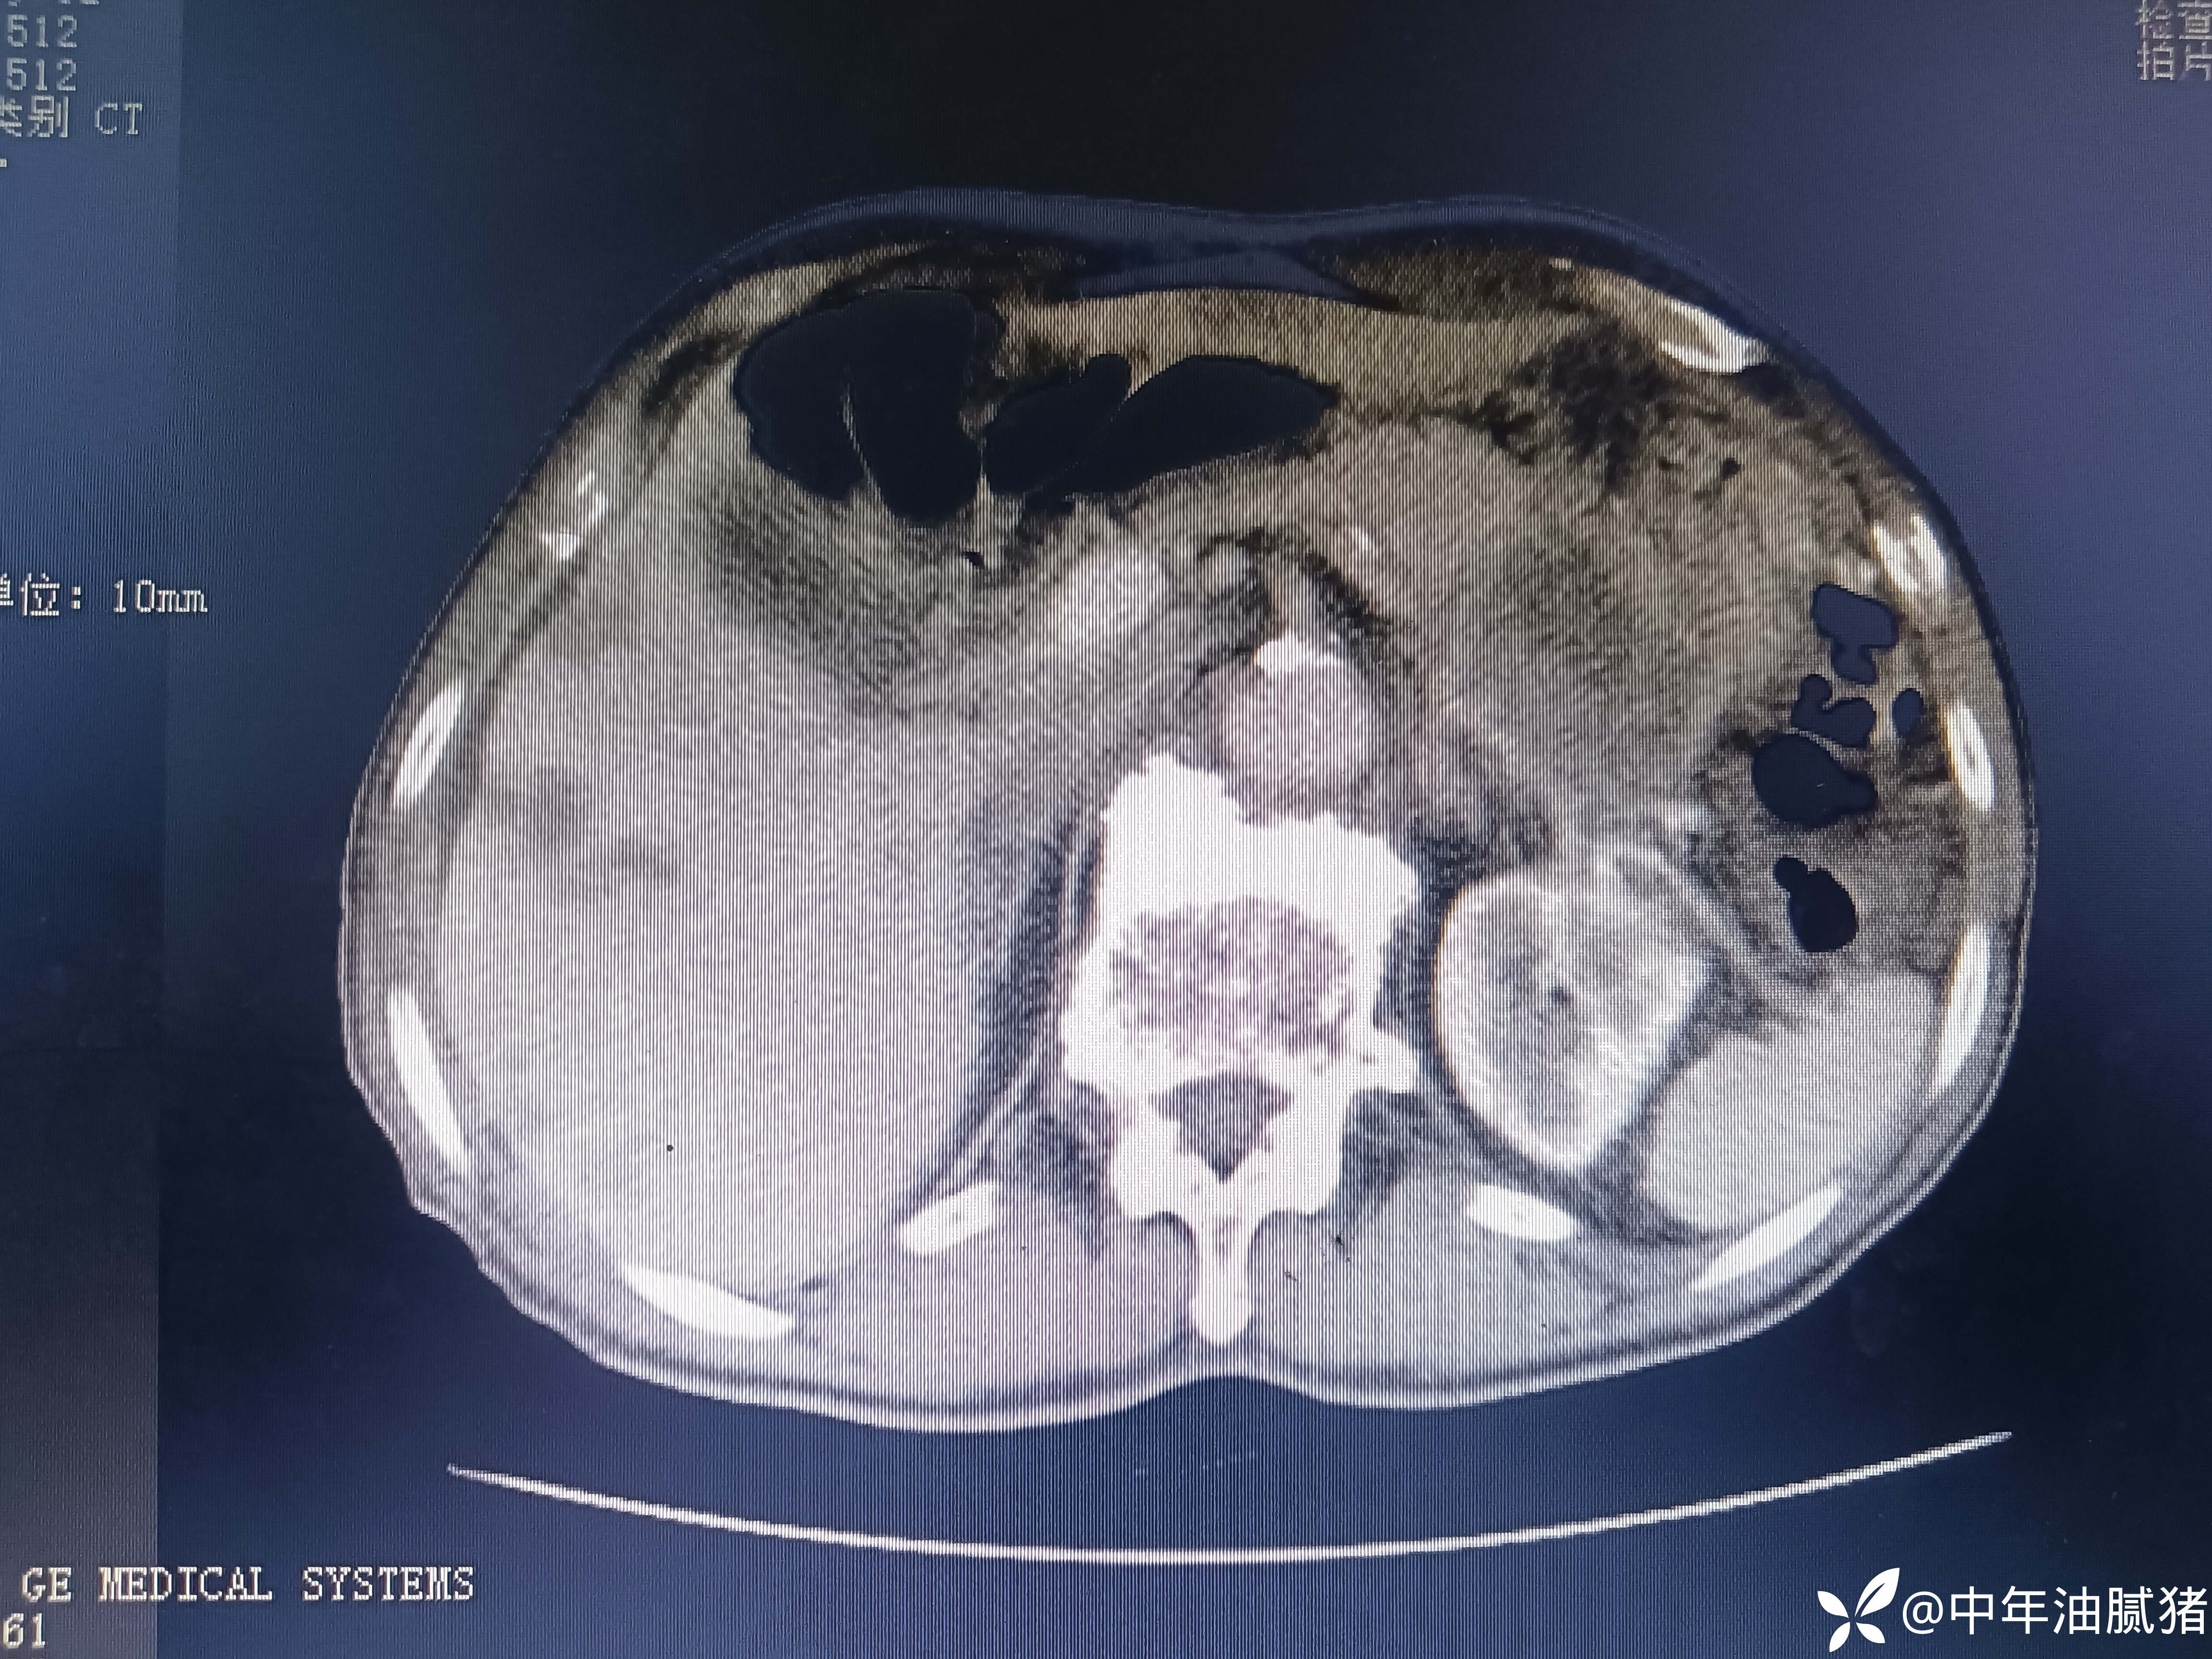

肺ct看到肝内病灶,行增强检查

建议增强ct.报告如下

考虑肝囊肿?让他走?

看后,我隐隐约约觉的不是肝囊肿那么简单?元芳,你怎么看?狄阁老,我也是这么认为!摇人,掏起手机:喂,w主任,请帮我看看这个ct。5分钟后报告修改如下